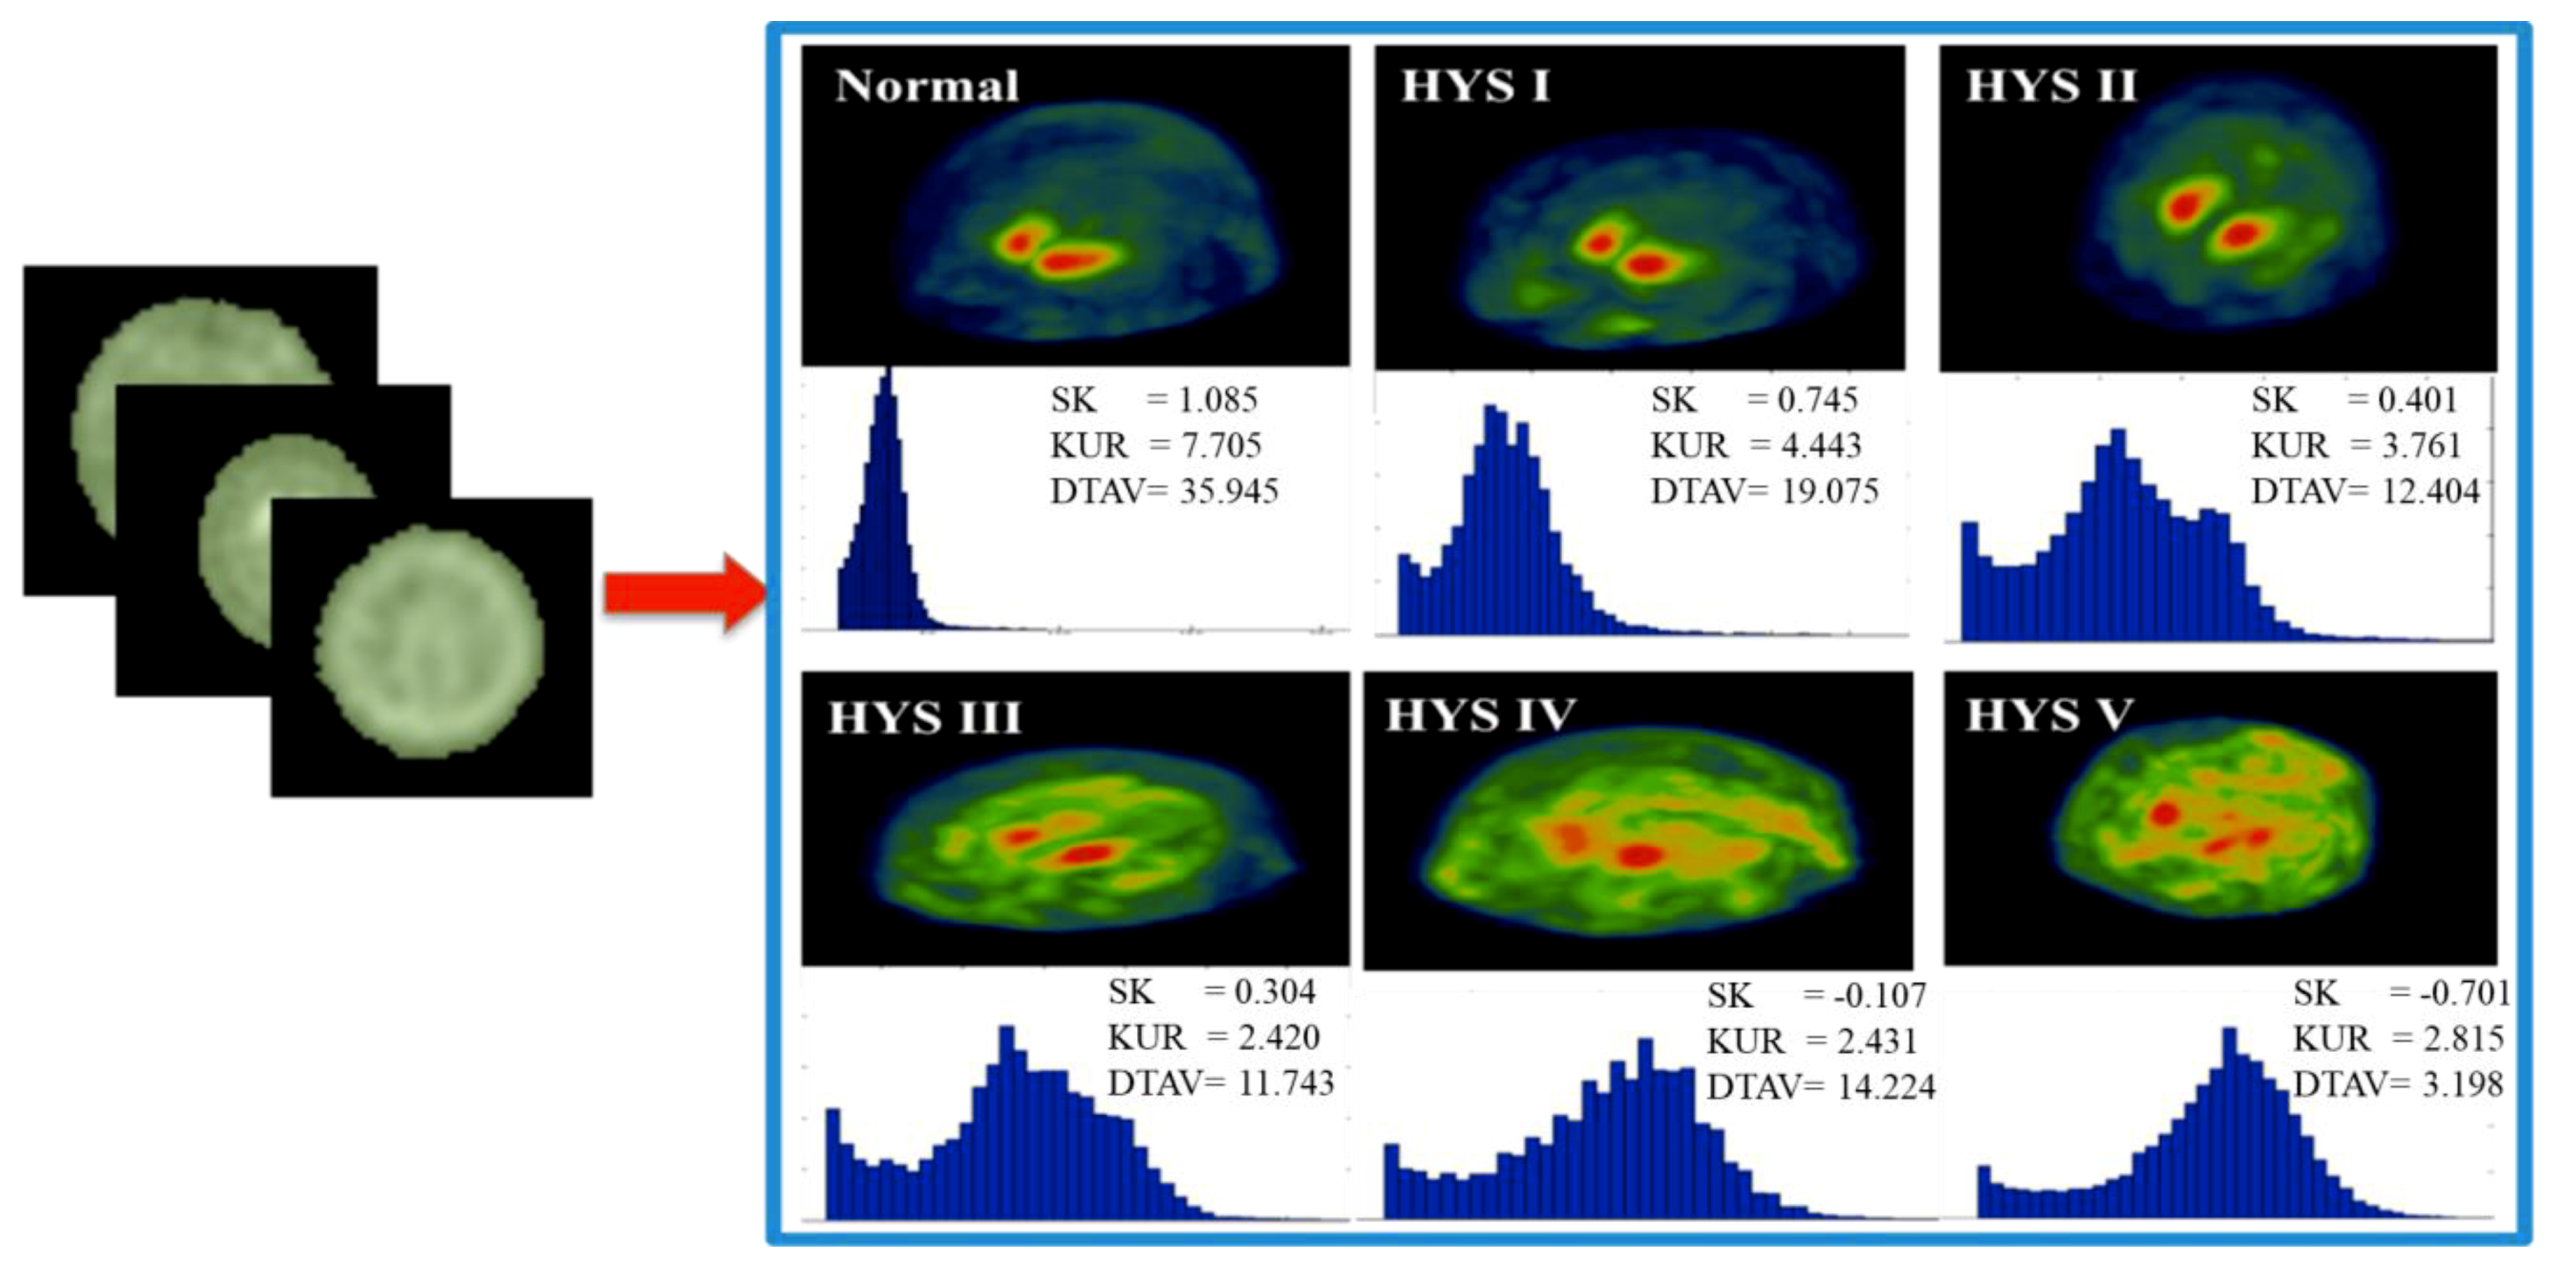

2.3. Experimental Design

3. Results